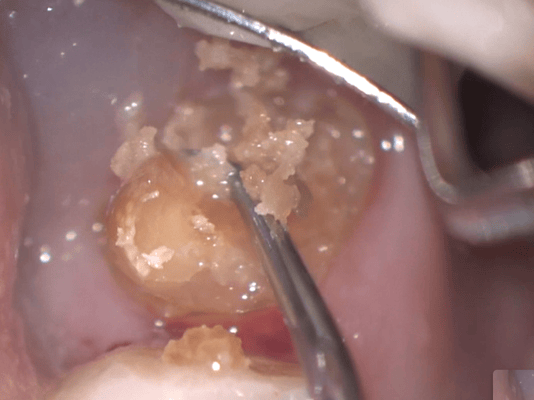

このように大きな虫歯でも、丁寧に虫歯(軟化象牙質)を除去していくと、第三象牙質の形成を伴って狭少になった歯髄腔の中の歯髄がまだ生きていることがわかります。術前の歯髄診断でも生活反応はありましたが、このような実際の状態をみると、歯髄診断の仕方も難しいなと思います。